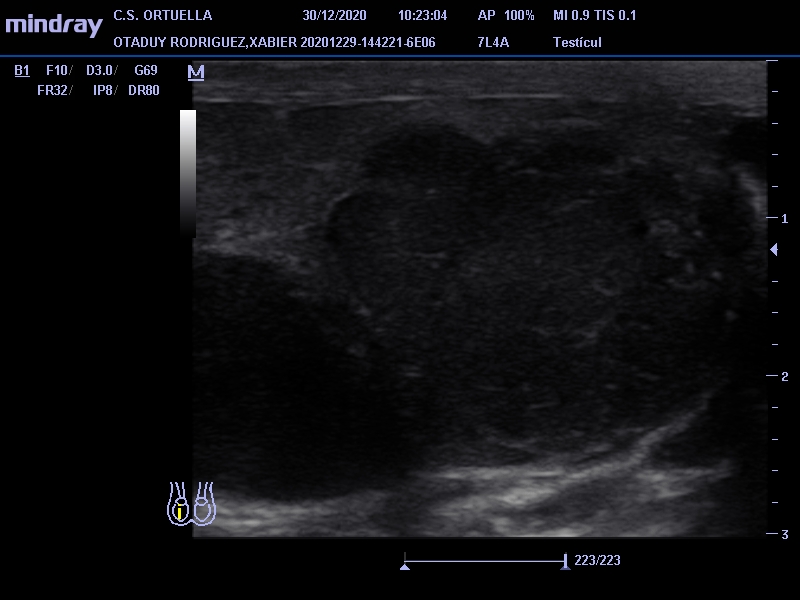

Hallazgos ecográficos

Masa de 38 x 40 mm, hipoecogénica, con aumento de vascularización mediante doppler, en polo inferior de teste derecho.